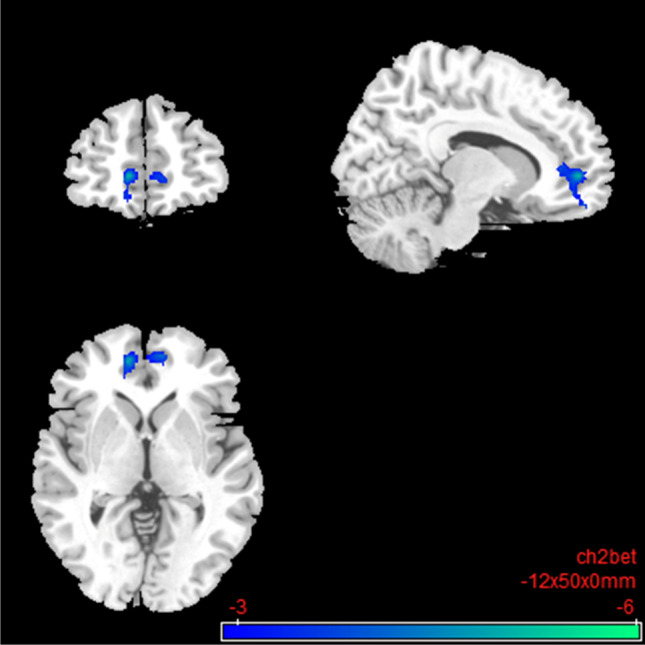

Under nalmefene, the insular cortex showed reduced connectivity to a cluster of frontal (medial frontal and superior frontal gyrus) and paralimbic brain regions (anterior cingulate gyrus and dorsal ACC; Table 4; Fig. 8). Under nalmefene, the ACC showed an elevated rsFC to the right angular gyrus as well as middle temporal gyrus, superior temporal gyrus, inferior temporal gyrus, and parahippocampal gyrus (Table 5; Fig. 9).

Fig. 8.

Salience network: brain regions with decreased resting-state functional connectivity between the seed region “left insular cortex” and the rest of the brain after 18 mg nalmefene compared to placebo (contrast: nalmefene > placebo, MNI coordinates: − 12 50 00). Combined voxel-wise-threshold (p < .01) and cluster-extent threshold k > 388 Voxel, corresponding to pFDR < .05